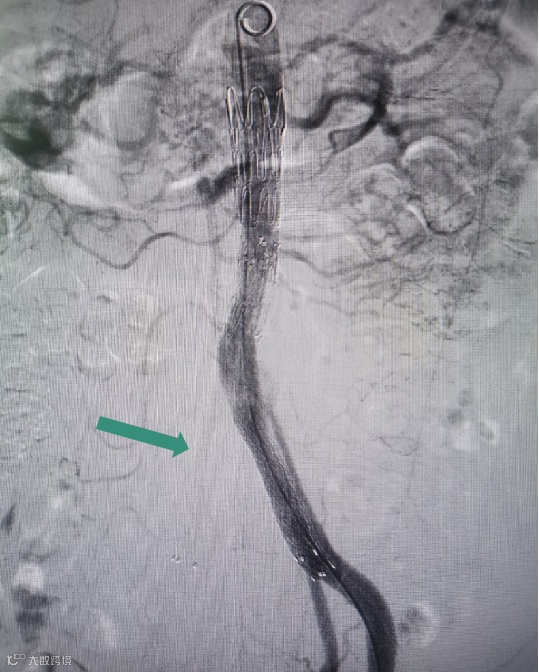

Separator With Aspiration catheter for Mechanical Thrombectomy(MT)【分离器辅助导管抽吸技术】:旨在提高整体系统的抽吸效率和治疗安全性,快速帮助血栓清除。

1)抽吸导管头端堵管,分离器可以快速疏通导管,降低撤管冲洗的频率。

2)针对大负荷血栓或亚急性血栓,分离器辅助下抽吸能提升整体系统抽吸效率,缩短手术时间。